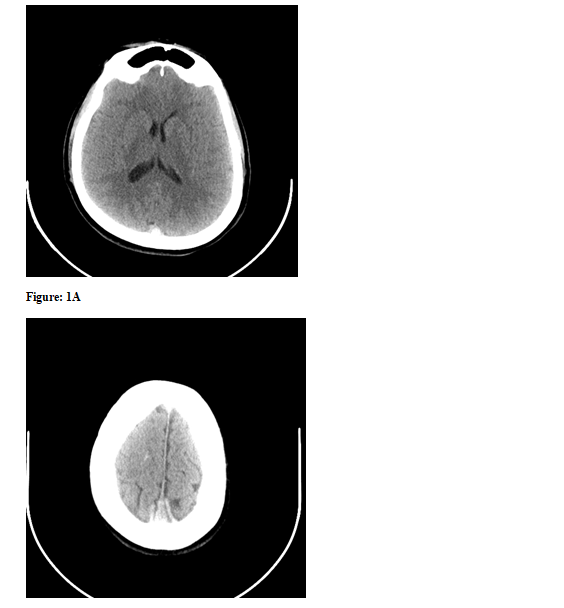

Various imaging techniques are used to confirm the diagnosis with CT angiography and MRI/MRV being most sensitive and specific. Approximately 30% of patients will also have some form of hemorrhage identified on initial imaging [4]. Most are small, low-pressure intra parenchymal hemorrhages of venous origin. Unfortunately, initial non-contrast head CT is normal in nearly 30% of patients with CVST [4]. Nonspecific changes such as focal edema, venous infarction, dilated veins, small ventricles, and subtle diffuse edema may be present. The “Dense Triangle Sign” is a hyperdense triangular or round shape in the posterior superior sagittal sinus that has been described in non-contrast head CT scans (Figure 1).

Plain CT scan headwith the round shape (A) or dense triangle (B) in the posterior superior sagittal sinus

Figure 1B: Plain CT scan headwith the round shape (A) or dense triangle (B) in the posterior superior sagittal sinus